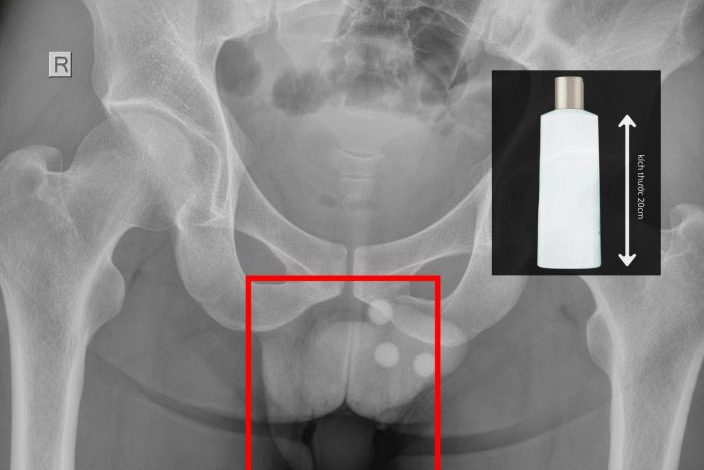

Ngày 8/3, bác sĩ chuyên khoa II Nguyễn Vũ An (chuyên khoa Ngoại tổng quát, tỉnh Tây Ninh) cho biết đơn vị vừa cấp cứu một người đàn ông nhập viện trong tình trạng đau rát dữ dội vùng hậu môn. Qua thăm khám, các bác sĩ phát hiện một chai nhựa dài khoảng 20cm mắc kẹt sâu trong trực tràng của người bệnh. Dị vật này tiềm ẩn nguy cơ gây thủng ruột và nhiễm trùng nặng nếu không được xử trí kịp thời.

Qua thăm khám và chụp X-quang, bác sĩ xác định dị vật nằm sâu trong trực tràng và không thể lấy ra bằng các thủ thuật thông thường. Ê-kíp đã tiến hành gây tê tủy sống, nong hậu môn và cẩn trọng lấy dị vật ra ngoài.

Theo bác sĩ An, dị vật chưa làm thủng trực tràng nhưng đã gây xây xát niêm mạc. Sau can thiệp, bệnh nhân được theo dõi, điều trị kháng sinh và chăm sóc hậu phẫu.